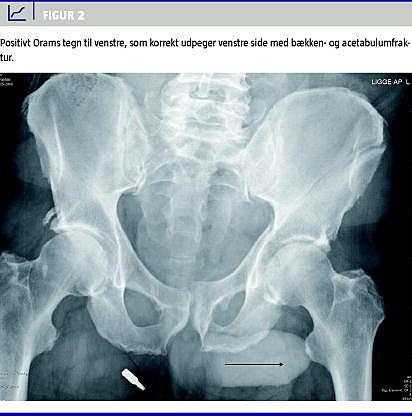

Troværdige og simple noninvasive diagnostiske test til at stille frakturdiagnoser har altid været efterspurgt i klinikken. I den forbindelse har der igennem tiderne været afprøvet mange forskellige metoder -f.eks. påsætning af stemmegaffel og samtidig auskultation på mistanke om hofte-, femurskaft- eller tibiaskaftfraktur [1], simpel perkussion af patella og samtidig auskultation over symfysen for at screene for hoftefraktur [2], og ultralydsskanning af os schaphoideum for at afsløre fraktur [3]. Orams tegn for hoftefraktur er en test, der har været kendt i flere år under forskellige betegnelser [4, 5], men som efter vores opfattelse endnu ikke er blevet regelret evalueret. Det såkaldte Orams tegn (Figur 1 og Figur 2 ) udsiger, at penis peger mod den patologiske side, det vil sige den side, hvor der er hofte- eller bækkenlidelse på et -standard, antero-posteriort (AP) røntgenbillede af bækkenet. Orams tegn har fra Orams tid i det daglige kliniske arbejde - og især ved røntgenkonferencerne - været anset for en værdifuld hjælp til at uddrage så mange oplysninger som muligt af disse røntgenundersøgelser, der foretages på så mange ortopædkirurgiske patienter og helt rutinemæssigt på ikke mindst de mange hoftefrakturpatienter. Selv om overlæge Oram var både dr.med. og dr.phil., har han ikke selv publiceret videnskabelige undersøgelser vedrørende validiteten af Orams tegn. Fra udlandet foreligger der enkelte beskrivelser af enkelte test, der dog er begrænset til udsigelser om hoftefrakturpåvisning [4, 5]. Vi har derfor følt et behov for en stringent videnskabelig evaluering af testens reliabilitet og validitet i en relevant klinisk sammenhæng, idet vi mener, at der kunne være mulighed for helt at undgå røntgenundersøgelse, hvis tegnet viste sig at være validt.

Studiet er retrospektivt og designet som et multibedømmerstudie, men med fokus på reliabilteten af testen hos den enkelte bedømmer er alle styrkeberegninger udført som beregning af det mindste antal test, der kræves for at kunne vise en diagnostisk forskel mellem to test hos en bedømmer [6]. Med et ønske om en sensitivitet for testen på mindst 83%, en specificitet på mindst 60% og en positiv likelihood ratio på 2,96, er der udført styrkeberegning på baggrund af 95%-konfidensintervallet omkring likelihood ratio . Analysen af stikprøvestørrelsen er udført som beskrevet af Simel et al 1991 [7] og er beregnet til 53. For at vurdere testens anvendelighed over for et helt normalt bækkenrøntgen, blev der yderligere medtaget ni optagelser uden frakturer eller anden patologi, hvoraf to optagelser var af kvinder. I studiet indgik således AP-optagelser af bækken fra i alt 62 patienter (60 mænd og to kvinder). Alle røntgenbilleder blev tilfældigt udvalgt fra Århus Sygehus' røntgendatabase af en uafhængig bedømmer og printet på papir af god kvalitet. Alle personhenførbare data, frakturer og kontralaterale side blev maskeret, således at bedømmelsen af røntgenbillederne blev gennemført blindet for alle parametre udover sidebestemmelse af Orams tegn. Fire erfarne mandlige speciallæger i ortopædkirurgi gennemgik billederne hver to gange uafhængigt af hinanden med et passende tidsinterval. For at vurdere en eventuel kønsbestemt observatørbias blev billederne også bedømt en gang af en rutineret ikkeortopædkirurgisk kvindelig speciallæge. Der var således i alt ni observationer af hvert røntgenbillede. Ved evaluering af et røntgenbillede havde bedømmerne fire svarmuligheder: 1) Orams tegn positivt til højre side (Figur 1), 2) Orams tegn positivt til venstre side (Figur 2), 3) Orams tegn neutralt (penis bedømmes at pege lige op eller lige ned i midtlinjen (Figur 3 ) og 4) ikke muligt at bedømme Orams tegn. Validiteten af testen blev evalueret ved beregning af testens sensitivitet, specificitet samt likelihood ratio , idet de frakturer/lidelser i bækken eller hofte, som var diagnosticeret ved den rutinemæssige røntgendiagnostik, blev brugt som gylden standard. Endelig blev reliabiliteten som inter- og intraobservatørvariation evalueret ved beregning af kappakoefficienter. Som database er anvendt Epidata 3.1, og alle analyser er udført i Stata 9.2.